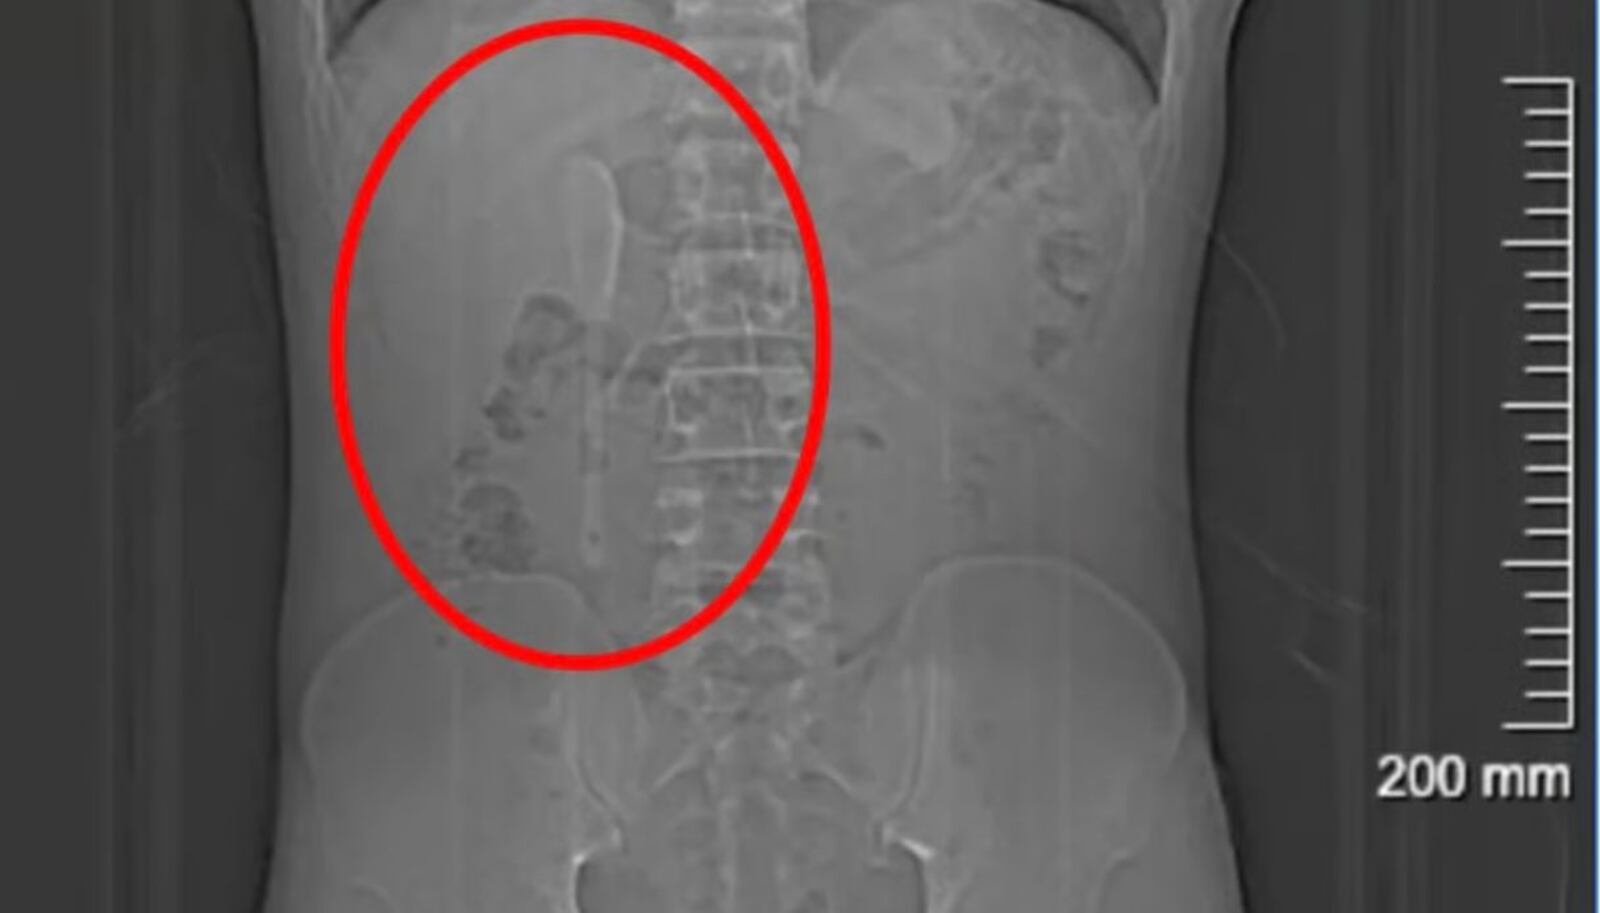

| Exame mostra colher no duodeno do chinês Yan, de 29 anos Reprodução/QQ/via R7 |

Incrivelmente, Yan seguiu sua vida normalmente por cinco meses, inclusive praticando exercícios físicos, sem apresentar sintomas graves. Foi só em junho, desconfiando ter ingerido algum plástico com comida de delivery, que ele procurou um hospital em Xangai. Os exames confirmaram a presença da colher, que estava em uma posição delicada, representando risco de perfuração, inflamação ou hemorragia.